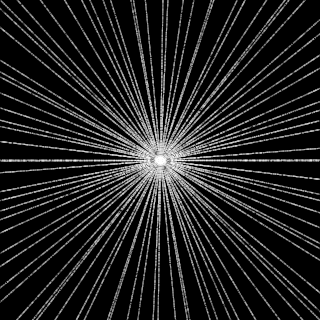

This article presents a novel undersampled magnetic resonance imaging (MRI) technique that leverages the concept of Neural Radiance Field (NeRF). With radial undersampling, the corresponding imaging problem can be reformulated into an image modeling task from sparse-view rendered data; therefore, a high dimensional MR image is obtainable from undersampled $k$-space data by taking advantage of implicit neural representation. A multi-layer perceptron, which is designed to output an image intensity from a spatial coordinate, learns the MR physics-driven rendering relation between given measurement data and desired image. Effective undersampling strategies for high-quality neural representation are investigated. The proposed method serves two benefits: (i) The learning is based fully on single undersampled $k$-space data, not a bunch of measured data and target image sets. It can be used potentially for diagnostic MR imaging, such as fetal MRI, where data acquisition is relatively rare or limited against diversity of clinical images while undersampled reconstruction is highly demanded. (ii) A reconstructed MR image is a scan-specific representation highly adaptive to the given $k$-space measurement. Numerous experiments validate the feasibility and capability of the proposed approach.